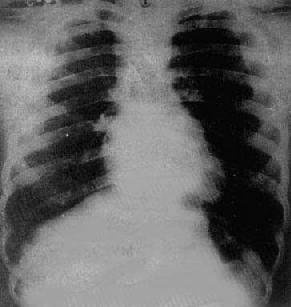

四联症分为三型,X线表现如下:

(1)常见型:(图3-2-22)肺动脉狭窄较重,室间隔缺损较大,紫绀明显。X线表现为①心一般无明显增大,心尖圆钝、上翘呈羊鼻状,心腰凹陷,如有第三心室形成,则心腰平直或轻度隆起;②右心室增大;③左心室因血流量减少而缩小,左心房一般无改变,右心房由于回心血流增多及右心心室压力增高而有轻度到中度增大;④肺门缩小,肺野血管纹理纤细;⑤主动脉增宽,并向前、向右移位。

图3-2-22 Fallot四联症

心增大,心尖圆钝上翅,心腰平直,右心室增大,

肺门缩小,肺纹理纤细,稀少